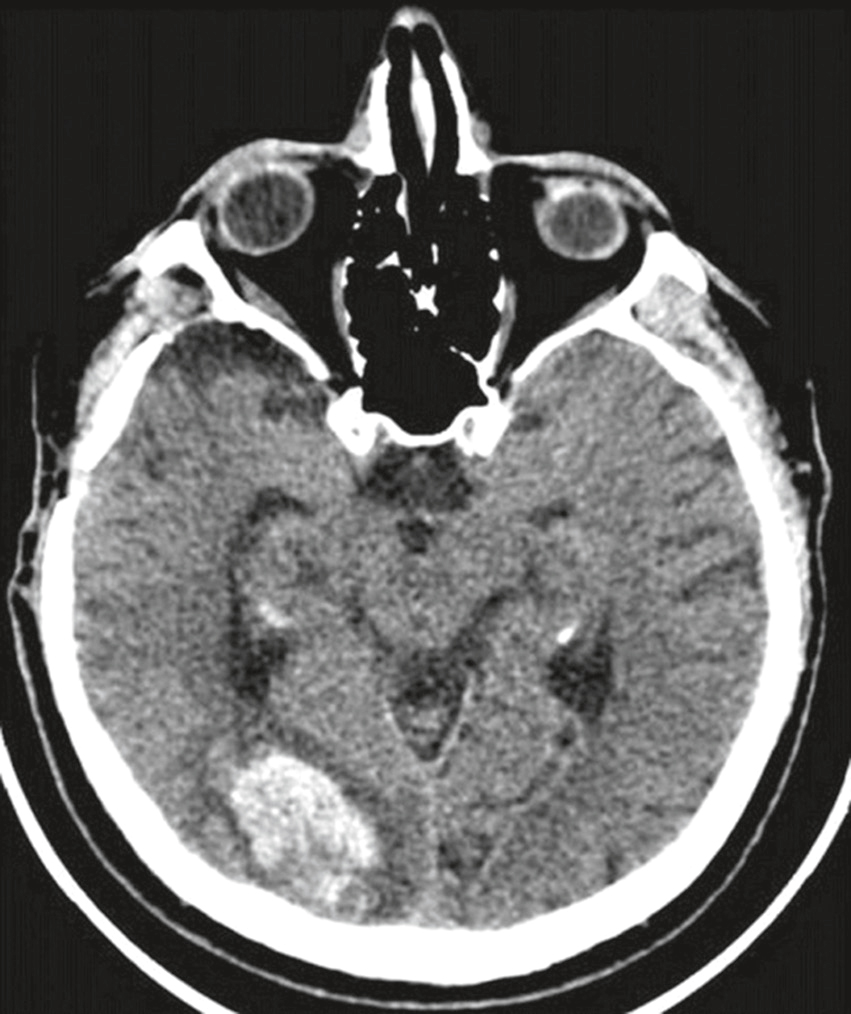

Une patiente de 85 ans, droitière, hypertendue traitée, est amenée aux urgences pour trouble neurologique de début brutal. L’imagerie suivante est réalisée (fig. 32.5). Sur cette imagerie, quel(s) est (sont) le (les) signe(s) compatible(s) avec cette atteinte ?

Coupe axiale d’un scanner cérébral sans injection de contraste mettant en évidence une hémorragie intraparenchymateuse temporale gauche. La collection hyperdense occupe une partie du lobe temporal médian, avec un effet de masse marqué sur les structures adjacentes. On observe un effacement des sillons corticaux de l’hémisphère gauche et une compression des cornes temporales gauches du ventricule latéral, traduisant une hypertension intracrânienne locale. L’aspect évoque un saignement spontané, probablement hypertensif ou lié à une malformation vasculaire sous-jacente. Il n’y a pas de signes immédiats de saignement intraventriculaire ou sous-arachnoïdien sur cette coupe.